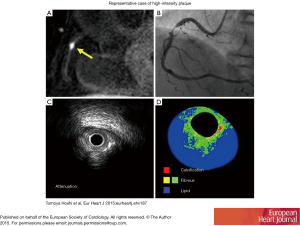

The feasibility of coronary plaque imaging was demonstrated by Fayad and expanded upon by Botnar (42,43). Since then using knowledge from carotid plaques [where plaque hemorrhage and lipid rich necrotic cores manifest as high signal intensity on T 1 weighted (T1W) sequences], Kawasaki has evaluated the components of High intensity plaque (HIP) on MRI and compared these with IVUS/CTCA demonstrating higher frequency of PR by both CTCA (89% vs. 0%, P<0.0001) and IVUS (94% vs. 14%, P<0.001) and ultrasound attenuation (100% vs. 14.3%, P<0.0001) (44). Importantly, Noguchi et al have shown the prognostic value of these HIPs. In a study of 568 patients with known or suspected CAD, the plaque to myocardium signal intensity ratio (PMR) was calculated. Plaques with PMR ≥1.4 independently predicted coronary events [HR: 3.96 (95% CI, 1.92−8.17), P<0.001] compared with the presence of CAD [HR: 3.56 (95% CI, 1.76−7.20), P<0.001] and traditional risk factors (45). Although plaque characterization by T1W MRI is technically demanding and its use is currently limited to research centers, corroborating data has been published by this group, where they showed that statin therapy reduces the PMR by comparison between propensity-matched cohorts (46).

Hoshi and colleagues demonstrated the feasibility of CMR findings in predicting PMI, where PMI occurred more frequently in the HIP than non-HIP group (58.1% vs. 10.9%, P<0.001) and that using a PMR >1.4 was a significant predictor of PMI (OR: 5.63; 95% CI, 1.28−24.7, P=0.022) (52). A representative image of HIP (A), angiographic stenosis (B), IVUS attenuation (C) and IB-IVUS (D) is shown in Figure 2 (52). These results further validated by Asaumi showing a PMR >1.3 cutoff (OR) predicted PMI with a sensitivity and specificity of 67% and 86% respectively (88).